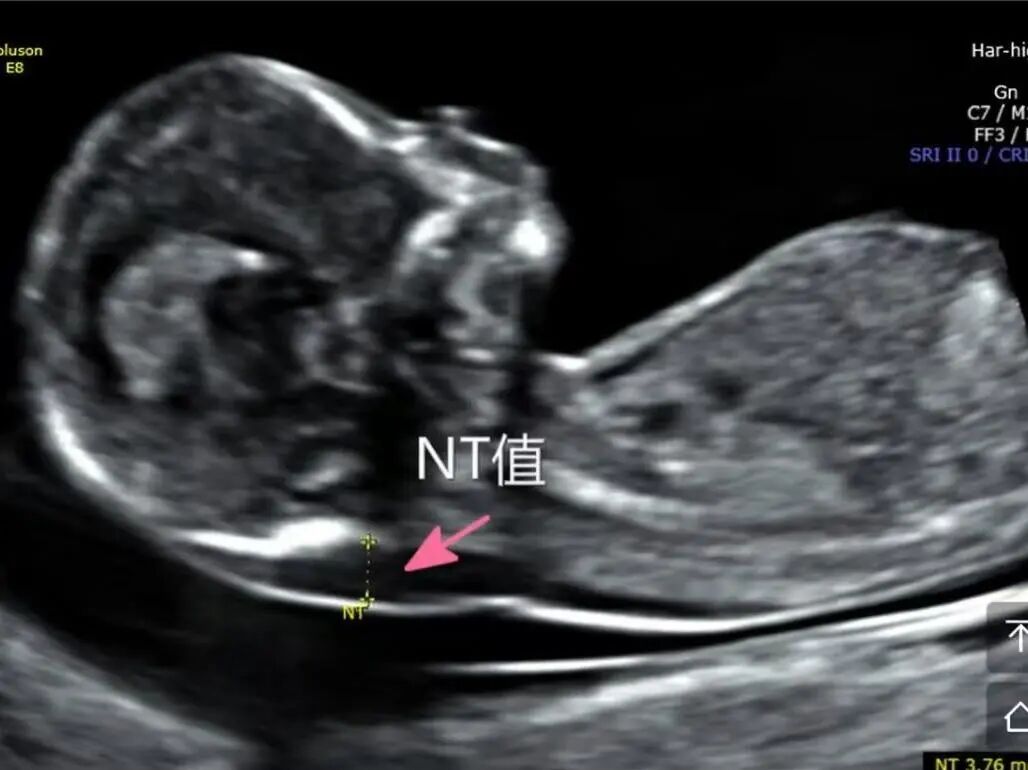

多年来,贵州航天医院各科室紧跟医学前沿,不断强技术、补短板,大力开展新技术、新项目,完成了许多高精尖、高难度、本地区“首例”的技术,填补了医院医疗技术空白,满足了群众日益增长的医疗需求。 复杂性双胎超声监护耗时耗力,技术难度大,风险高,为填补本地区复杂性双胎的超声监护技术空白,我院超声科在遵义市率先开展了此项技术,有效满足了双胎孕妇产检需求,保障了双胎新生儿的平安健康。 本期,我们将为大家带来超声科特色技术——复杂性双胎的超声监护。 案例分享 案例一 28岁的孕妇,自然受孕,怀有单绒毛膜双羊膜囊双胎(MCDA),在我院定期产检的过程中,孕32周超声检查发现两个胎儿的大脑中动脉血流流速(MCA-PSV)相差>0.7倍数的正常值(MoM),高度怀疑发生了双胎贫血红细胞增多序列征(TAPS)。为进一步明确诊断,产科立即组织超声科、手术室、新生儿科等科室进行多学科会诊(MDT),诊断为:双胎贫血红细胞增多序列征(TAPS),在征得孕妇及其家属的同意后,决定提前分娩,及时保障了两名胎儿的生命和健康。 双胎大脑中动脉血流 双胎贫血红细胞增多序列征(TAPS) 案例二 一名26岁的孕妇,是完全双角子宫,且为左侧子宫妊娠,怀有单绒毛膜双羊膜囊双胎(MCDA),一直在我院规律产检,孕16周时,超声检查发现双胎生长不一致,体重相差超过25%,考虑子宫畸形合并早发选择性胎儿宫内生长受限。孕妇在咨询相关上级医院专家后,得到减胎的建议,又前来我院咨询,在我院超声科和产科的合作下,查阅了大量文献、认真评估检查报告后,建议孕妇继续双胎妊娠。在规律、严密的超声监护下,双胎除体重差异外未出现严重胎儿并发症,在34周进行了分娩,截至目前,新生儿生长发育均正常。 胎儿生长曲线及子宫畸形三维重建 出生时体重差异 十月龄时 案例三 一名30岁的孕妇,自然受孕,怀有单绒毛膜双羊膜囊双胎(MCDA),在孕22周时超声检查发现双胎发生了选择性胎儿宫内生长受限,遂转诊到上级医院拟行胎儿镜治疗,但在行治疗的前一天,较小的胎儿在宫内发生死亡,在充分与孕妇及家属沟通后,要求继续妊娠,在定期规范的产检下,严密监测胎儿生长发育及胎儿颅脑MRI影像,最终在孕37周时通过剖宫产分娩,目前新生儿生长发育情况良好。 双胎之一胎死宫内(右图) 贵州航天医院自2021年开展复杂性双胎的超声监护以来,已服务大量双胎孕妇,集齐了所有单绒毛膜双羊膜囊双胎(MCDA)并发症病例,由经验丰富的超声医师进行此项检查,产科专业团队进行双胎的规范化监护和分娩,并与重庆医科大学附属第一医院建立了转诊通道,能够及时获得该院专家的指导和支持,为广大孕产妇提供优质、全面的医疗保障。 点击跳转贵州航天医院便民服务电话 什么是复杂性双胎的超声监护 “双胎”被称为产科之王,单绒毛膜双胎则为王中王,主要是因为单绒毛膜双羊膜囊双胎(MCDA)两胎儿共用一个胎盘,胎盘中存在血管吻合。 双胎妊娠的产前筛查及诊断主要依靠超声,相对于单胎妊娠,双胎妊娠并不是单胎检查的重复,双胎妊娠尤其是复杂性双胎的超声诊断更为重要的是关注双胎间循环的关联,双胎间生理及病理改变的相互影响,双胎间血流动力学监测及双胎间差异比较。 超声如何诊断 复杂性双胎并发症 在孕14周以前,超声要明确双胎的绒毛膜性:是单绒毛膜(MC)还是双绒毛膜(DC);孕10周前,可以通过孕囊的个数确定绒毛膜性;孕11周—14周,可以通过胎儿的性别、双胎之间隔膜的厚度、双胎儿分隔膜处胎盘的形态等来区分绒毛膜性。 双绒毛膜双胎的管理和单胎差不多,基本不需要增加超声检查的频次。单绒毛膜的管理相对谨慎,按照国际国内指南规范,单绒毛膜双胎自第16周起,每两周对双胎儿进行生长发育评估及血流检查。 复杂性双胎的超声监护,对超声医生技术要求较高,孕早期需对双胎的绒毛膜性进行精确判断;产科医生根据绒毛膜性制定孕期的产检计划;超声医生掌握胎儿宫内情况,及时与产科医生沟通,精确了解胎儿宫内安危后制定合适的治疗方案,给出适当的终止妊娠时机;复杂性双胎一般都面临早产的风险,所以新生儿团队的专业保障不可或缺,降低新生儿出生后的并发症及提高新生儿生活质量。复杂性双胎的较好妊娠结局,是通过孕期超声科、产科紧密合作,及新生儿出生后新生儿科管理多学科团队合作所获得的。 贵州航天医院超声科专家团队 吴艳辉 超声科 学科带头人 主任医师 专业擅长:从事超声诊断工作约30年,对心血管、小器官超声、超声引导下介入等具有丰富的临床经验。 骆科美 超声科 副主任医师 专业擅长:从事超声诊断工作33年,对胎儿心脏及颅脑、妇产超声诊断、盆底超声等诊断具有丰富的临床经验。 胡大海 超声科 副主任医师 专业擅长:从事超声工作17年,对心血管、外周血管、浅表器官超声诊断等具有丰富的临床经验。 刘 敏 超声科 副主任医师 专业擅长:从事超声诊断工作20余年,对妇产科超声、心脏血管超声诊断具有丰富的临床经验。 贵州航天医院超声科简介 贵州航天医院超声科配备多种超声检查设备(飞利浦彩超(IU-22、IU-Elite、HD11、Q5、Q7),迈瑞超声I9、DC-6、DC-8、GE-E8及床旁机,彩色超声诊断仪等),设有心血管诊室、妇产科诊室、腹部诊室、绿色通道、浅表小器官等检查室。 • ✦ 专科特色 ✦ • 四肢血管超声检查、双胎产前筛查及超声监护、超声造影检查技术、介入超声临床应用、经颅脑实质超声辅助筛查诊断帕金森病、女性性早熟超声诊断、盆底超声检查等。 NT超声检查 超声介入引导 肝脏超声造影 甲状腺造影 颅脑超声帕金森辅助检查 乳腺超声造影 上肢动静脉造瘘超声检查 双胎超声筛查 下肢血管超声检查 右心造影 • ✦ 诊疗范围 ✦ • 科室业务覆盖腹部、泌尿、妇科、产科(常规、NT筛查、III级筛查超声检查及高危妊娠监护)、成人心脏、外周血管、浅表器官(包含甲状腺、乳腺、阴囊、眼睛等)、颅脑(小儿颅脑、成人颅脑)、小儿肺超、造影、盆底、腹直肌、肌骨神经等检查及各种介入引导。